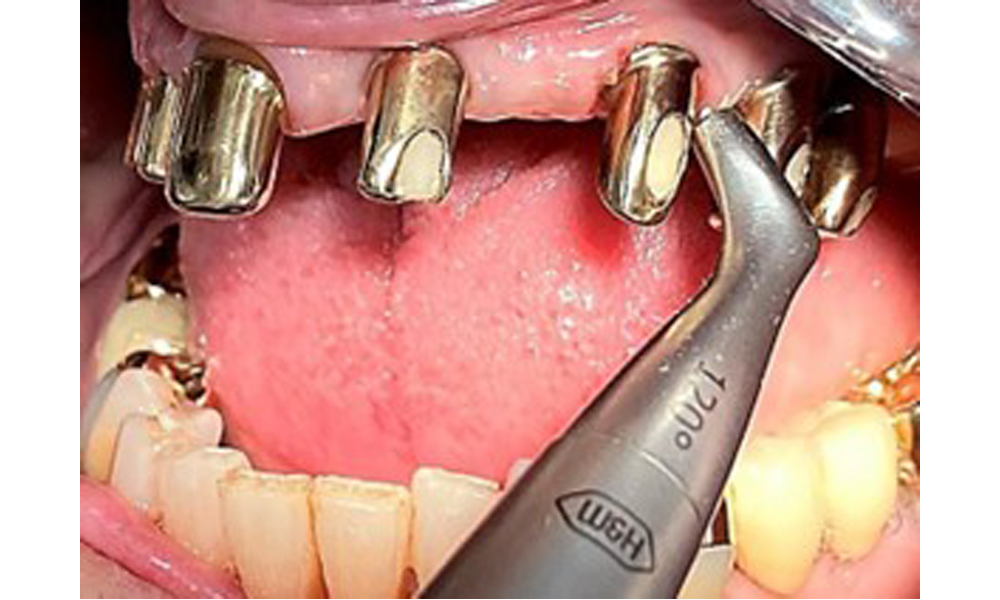

Bearbeitung der Implantatoberfläche mit Handinstrumenten aus Titan.

Abb. 10: Bearbeitung der Implantatoberfläche mit Handinstrumenten aus Titan.

Für die Entfernung von Zahnstein und Konkrementen am natürlichen Zahn kann Schall Ultraschall verwendet werden sowie konventionelle Handinstrumente (8). An den Implantaten sind für mineralisierte Beläge Titan- oder Kunststoffküretten (Abb. 10) einzusetzen oder ein Kunststoff- bzw. Peek-Ansatz (Abb. 11) für die Ultraschallbehandlung, um die Implantatoberfläche nicht zu beschädigen.